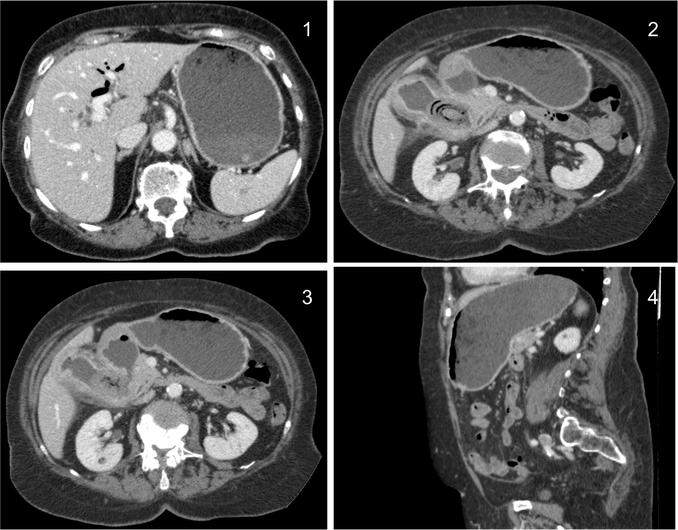

El íleo biliar se define como la obstrucción mecánica causada por la impactación en el lumen intestinal de una litiasis biliar procedente de la vesícula. Es una complicación que ocurre en el 0.3 – 0.5% de todas las colelitiasis.

Aunque su frecuencia global es baja, en pacientes ancianos no lo es tanto, llegando a constituir alrededor del 25% todas las obstruciones intestinales no estranguladas. Al igual que en la coletitiasis, es más frecuente en mujeres.

Su mortalidad varía entre el 8 -30%, llega a ser bastante alta sobre todo en ancianos con patología concomitante.

Placa simple: Triada de Rigler: Obstrucción de asas de delgado + gas en el arbol biliar + litiasis (frec en la FID); estos tres hallazgos constituyen la Triada de Rigler.

Tomografía computarizada: S y E del 93% y 100% respectivamente. Hallazgos: Dilatación por obstrucción de asas de delgado. Aerobilia. Litiasis (2 – 3 cm aprox). Hay que tener cuidado ya que muchas litiasis no están calcificadas y su densidad puede ser similar al contenido del intestino. Pueden ser multiples, por tanto hay que poner atención para que no pasen desapercibidas y evitar las recidivas. Fistulas (normalmente entre vesícula y duodeno). Neumoperitoneo (gas portal o gas mural indican peor pronóstico).

Sindrome de Bouveret: Es un tipo de íleo biliar muy proximal y poco frecuente, donde una litiasis migra a través de una fístula desde la vesícula biliar al duodeno proximal o al píloro gástrico, produciendo ahí una obstrucción.